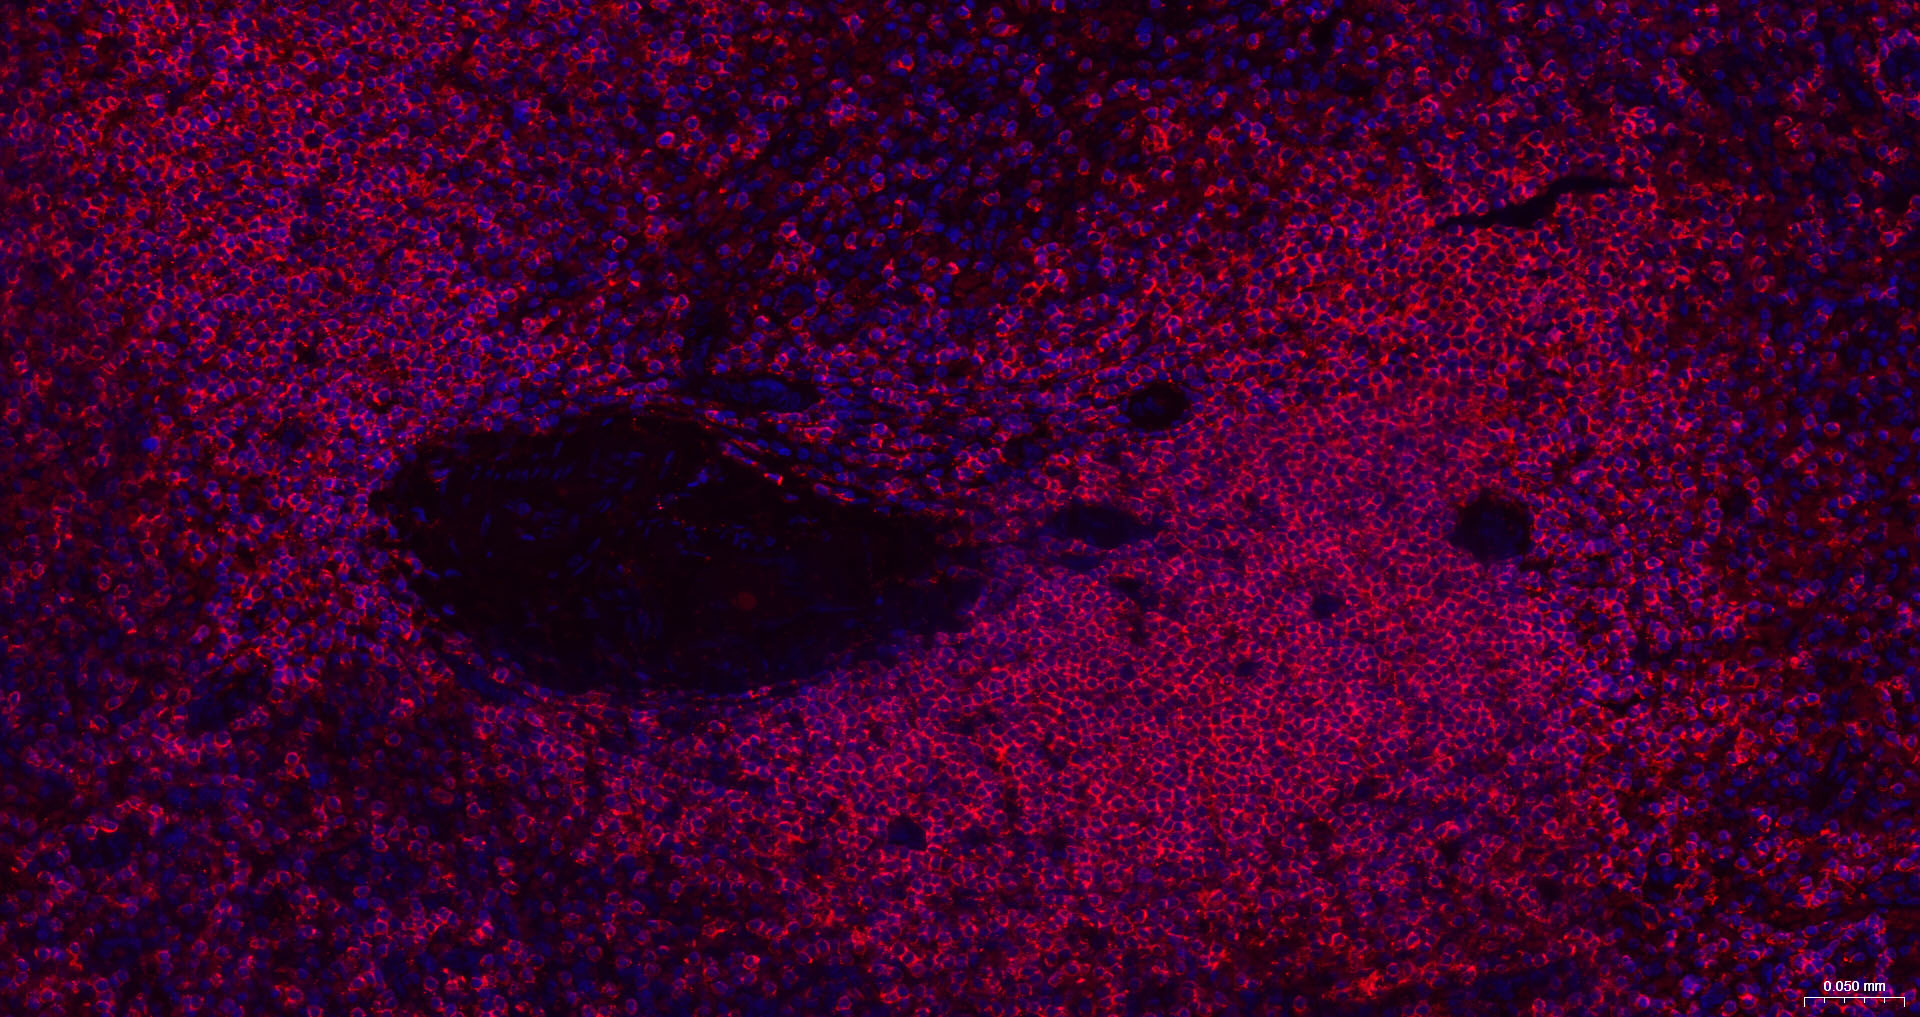

CD45 Recombinant Antibody

• IHC-F

• IF(IHC-P)

IHC-F IHC-F1:100-500

IF(IHC-P) IFIHC-P1:100-500